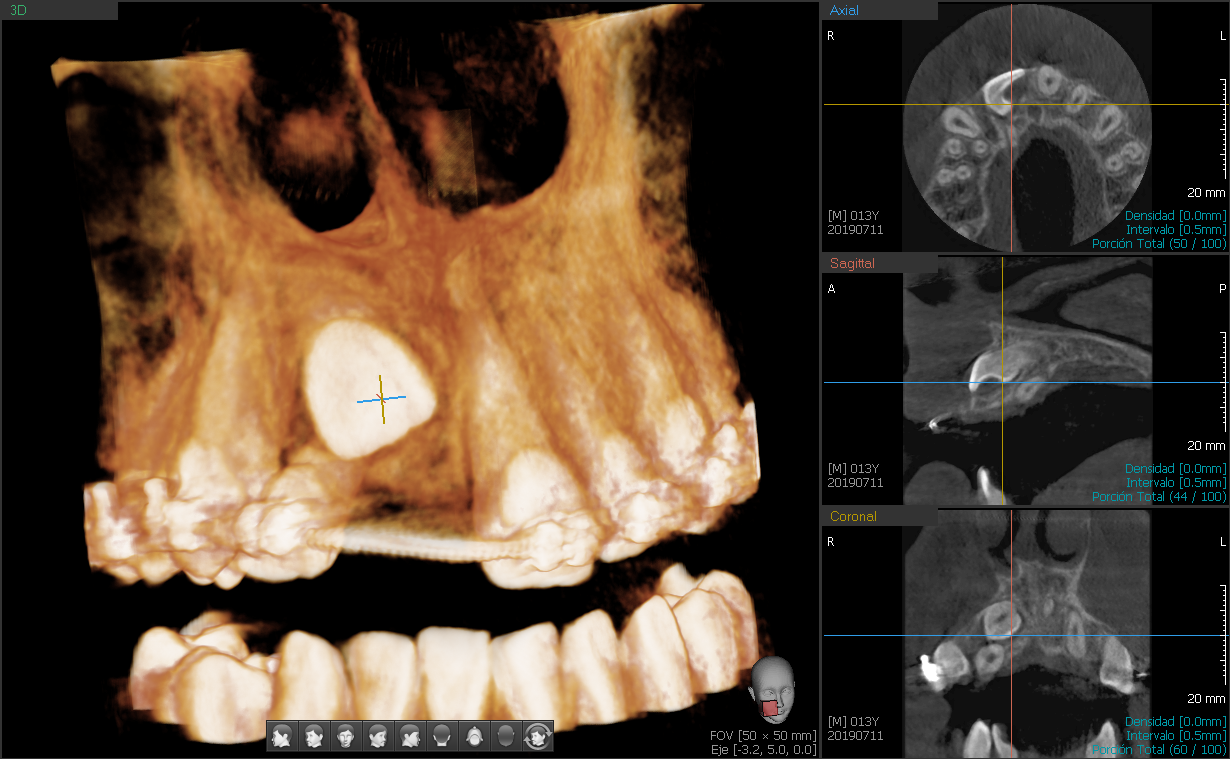

En Clínica Núñez nuestros especialistas en ortopedia dento-facial realizan estudios cráneo-métricos y fotográficos para diseñar tratamientos personalizados que guíen el desarrollo facial de los pacientes jóvenes.

- Tecnología avanzada: Utilizamos estudios cráneo-métricos y fotográficos para un diagnóstico preciso. Sistemas de diagnóstico y planificación mediante scaner intra-oral.